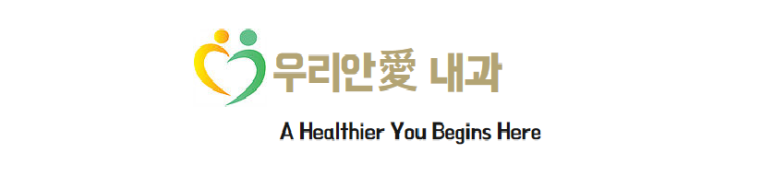

갑상선 초음파에서 오른쪽 갑상선 뒤쪽/아래로 결절?

위아래로 2개처럼 보이기도 하고..

2개가 아니라 연결되어 있으며 격벽처럼 관찰되는데... 1.75 cm

어두은 결절인지? 낭종인지? 구별이.. (낭종이 있을 위치가 아니라 생각을 하니..)

눌러보면 눌리지는 않으나.. 낭종으로 생각되며

연속 사진으로 내측의 경계가 불규칙하거나 격벽 변화가 있는 모습

확대하면 두꺼운 벽처럼 보이는 부분도 있다. 거꾸로 아래쪽 어두운 곳은 낭성 변화

Imaging included parathyroid ultrasonography, which revealed a cystic appearing mass with septations and mild irregularity (격벽과 불규칙한 내부 경계를 보이는 낭성 종괴)